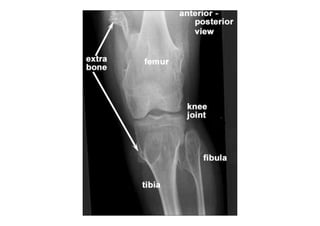

RADIOLOGIA DO

TRAUMA DO ESQUELETO

Referência: http://www.accessexcellence.org/RC/VL/